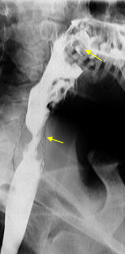

Diverticul medioesofagian complicat cu fistulă esobronșică

Diverticuli medioesofagieni

Diverticul medioesofagian complicat cu fistulă